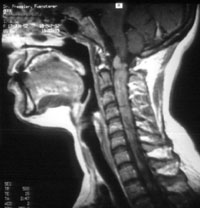

Ebenso häufig wie am Hörnerv finden sich spinale (das Rückenmark betreffende) Raumforderungen (in der Medizin bezeichnet der Begriff Raumforderung in vielen Fällen eine Gewebswucherung).

Bei den Patienten mit einer Neurofibromatose Typ 2 werden die cranialen (den Schädel betreffenden) Raumforderungen fast immer symptomatisch (z.Bsp. Hörminderung). Die spinalen Raumforderungen werden aber nur in ca. 40 % der Fälle symptomatisch.

Die spinalen Tumoren werden in zwei Gruppen unterteilt.

Einmal findet man intramedulläre Raumforderungen. Damit sind Tumoren gemeint, die sich in der Gewebssubstanz des Rückenmarkes finden. Hier findet man vor allem Astrozytome und Ependymome.

Zum anderen finden sich extramedulläre Raumforderungen. Hiermit meint man Tumoren oder Gewebsveränderungen, die sich im Rückenmarkskanal, aber außerhalb der Rückenmarkssubstanz befinden. Der extramedulläre Raum ist der Spalt zwischen der Oberfläche der Rückenmarkssäule und der knöchernen Wand des Rückenmarkskanales innerhalb der Wirbelsäule. In diesen Fällen treten vornehmlich Schwannome und Meningeome auf.

Geschwülste im Bereich der Wirbelsäule und des Rückenmarks Neurofibromatose häufig. Sie sind zumeist gutartig, die häufigsten Typen sind Neurinome (von Nervenscheiden ausgehend) und Meningeome (von den Rückenmarkshäuten ausgehend). Diese Tumore verursachen Symptome durch Druck auf das Rückenmark oder die davon ausgehenden Nervenwurzeln. Die Möglichkeiten einer vollständigen operativen Entfernung im Rahmen eines mikrochirurgischen Eingriffs sind sehr gut. Neurinome nehmen ihren Ausgang von den spinalen Nervenwurzeln und können sich durch die Wirbellöcher sogar nach außerhalb des Spinalkanals ausdehnen ("Sanduhrgeschwulst"). Sie kommen in allen Abschnitten des Spinalkanals vor und zeigen sich vorwiegend im mittleren Lebensalter. Meningeome gehen von den Rückenmarkshäuten aus und sind zu 80% thorakal lokalisiert.

Darüber hinaus gibt es Tumore, die im Rückenmark selbst wachsen wie Ependymome. Eine vollständige Entfernung dieser "intramedullären" Tumore ist oft aber gut möglich (insbesondere bei den genannten Ependymomen), auch wenn sie bei sehr ausgedehnten und infiltrierend wachsenden Tumoren im Einzelfall mit einem erhöhten Risiko einer postoperativen Lähmung verbunden sein kann. In diesen Fällen wird eine "innere Entlastung" geschaffen und eine Erweiterungsplastik der harten Hirnhaut angelegt, um einen maximalen Effekt bei minimalem Risiko zu erreichen. Der Funktionserhalt steht dabei immer im Mittelpunkt!